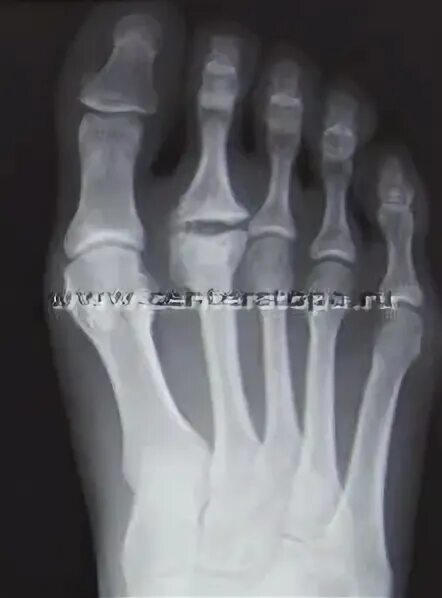

Болезнь шинца мкб 10